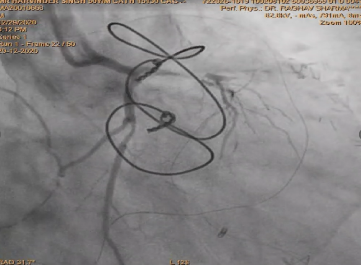

After deployment observed Perforation of SVG-OM Distal LCX post Stenting.

Used two covered stent to cover perforation OM and LCX .

After using covered stent perforation was sealed and TIMI 3 flow achieved